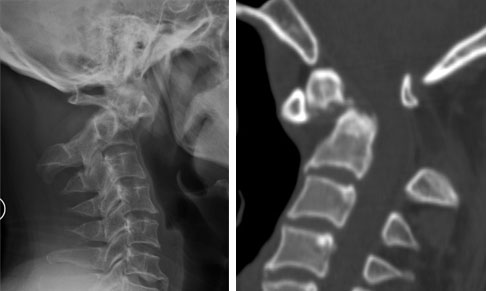

病例3  颈2齿状突陈旧性骨折并寰椎脱位,后路寰枢椎椎弓根螺钉复位固定融合术。

患者56岁,男性,颈2齿状突陈旧性骨折并寰椎脱位。

患者颈部外伤后2年入院,四肢肌力、感觉正常。

术后寰枢椎即可复位,术后患者四肢肌力、感觉正常。

术中使用电钻寰椎置钉道